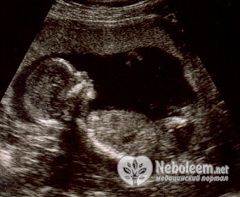

Если сделать УЗИ на 33 неделе беременности, то можно определить размеры будущего ребенка. Его длина составляет где-то 41 – 42 см, весит он от 1800 до 2200 г. В течение нескольких недель прибавки в весе ребенка будут довольно интенсивными.

По УЗИ на 33 неделе беременности можно заметить, что тело плода стало пропорциональное и больше похоже на новорожденного. Несмотря на компактную эмбриональную позу, ему все же стало тесновато в полости матки, поэтому движения его ощущаются в животе на 33 неделе беременности реже, но стали более сильными. Довольно много времени плод проводит во сне, но отсутствие шевелений в течение 12 часов – опасный прогностический признак для дальнейшей беременности.

Врач направляет женщину на УЗИ на 33 неделе беременности в том случае, если она не сделала его до этого срока, в 30 – 32 недели. При необходимости возможно проведение кардиотокографии, с помощью которой можно оценить, как меняются сокращения плода в ответ на мышечное напряжение матки.